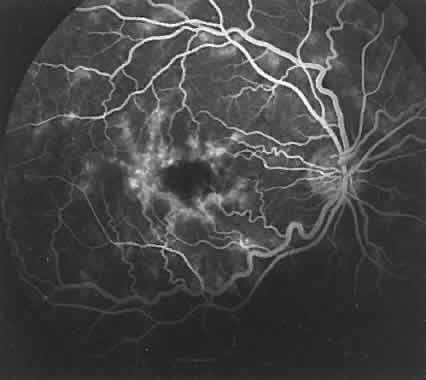

Central serous chorioretinopathy causes an area of hyperfluorescence because of the presence of the dye between the retinal photoreceptor cells and the RPE (Fig. 19). This may be related to a detachment of the RPE and is associated in some way to a defect in the normal mechanism of fluid exchange across the RPE between the choroid and the sensory retina. The attachment of the photoreceptors to the RPE may not be as strong as the attachment of the RPE to Bruch's membrane. This may be why the borders of fluorescence in the secondary serous retinal detachments found in central serous chorioretinopathy are more diffuse (see Fig. 19B) than those in a detachment of the RPE (see Fig. 18B).

Fig. 19. Hyperfluorescence in patient with central serous chorioretinopathy. A. Accumulation of fluorescein (black dots) between the neurosensory retina and the retinal pigment epithelium (RPE). There is also a small focal detachment of the RPE that is filled with fluorescein. B. Area of hyperfluorescence corresponding to serous detachment of neurosensory retina that has filled with fluorescein (white arrows). Within this area is a smaller, more hyperfluorescent site (black arrows), resulting from small focal detachment of the RPE.